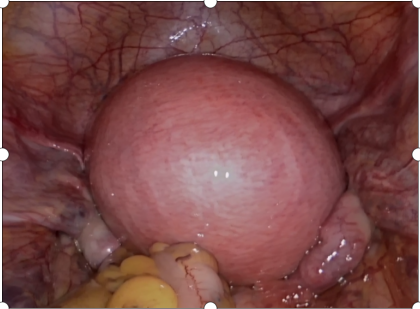

一場(chǎng)緊張又充滿懸念的“保宮”大戰(zhàn)在正興醫(yī)院手術(shù)室上演!術(shù)中腹腔鏡下張惠嬌主任先切除患者前哨淋巴結(jié),送快速冰凍病理切片檢查,結(jié)果為陰性;接著進(jìn)行子宮肌瘤剔除術(shù)+保留子宮的廣泛宮頸切除術(shù),將切除的宮頸上切緣再送冰凍病理切片檢查,仍為陰性。

至此陳女士具備了保留生育功能的條件,手術(shù)可以說是緊張而有序地進(jìn)行著,最后順利地完成了宮體部與陰道部的吻合,并于宮腔內(nèi)放置一帶有尾絲的宮內(nèi)節(jié)育器作為支撐,降低術(shù)后宮頸粘連的發(fā)生,實(shí)現(xiàn)了陳女士保留子宮的心愿。

△患者術(shù)后盆腔外觀